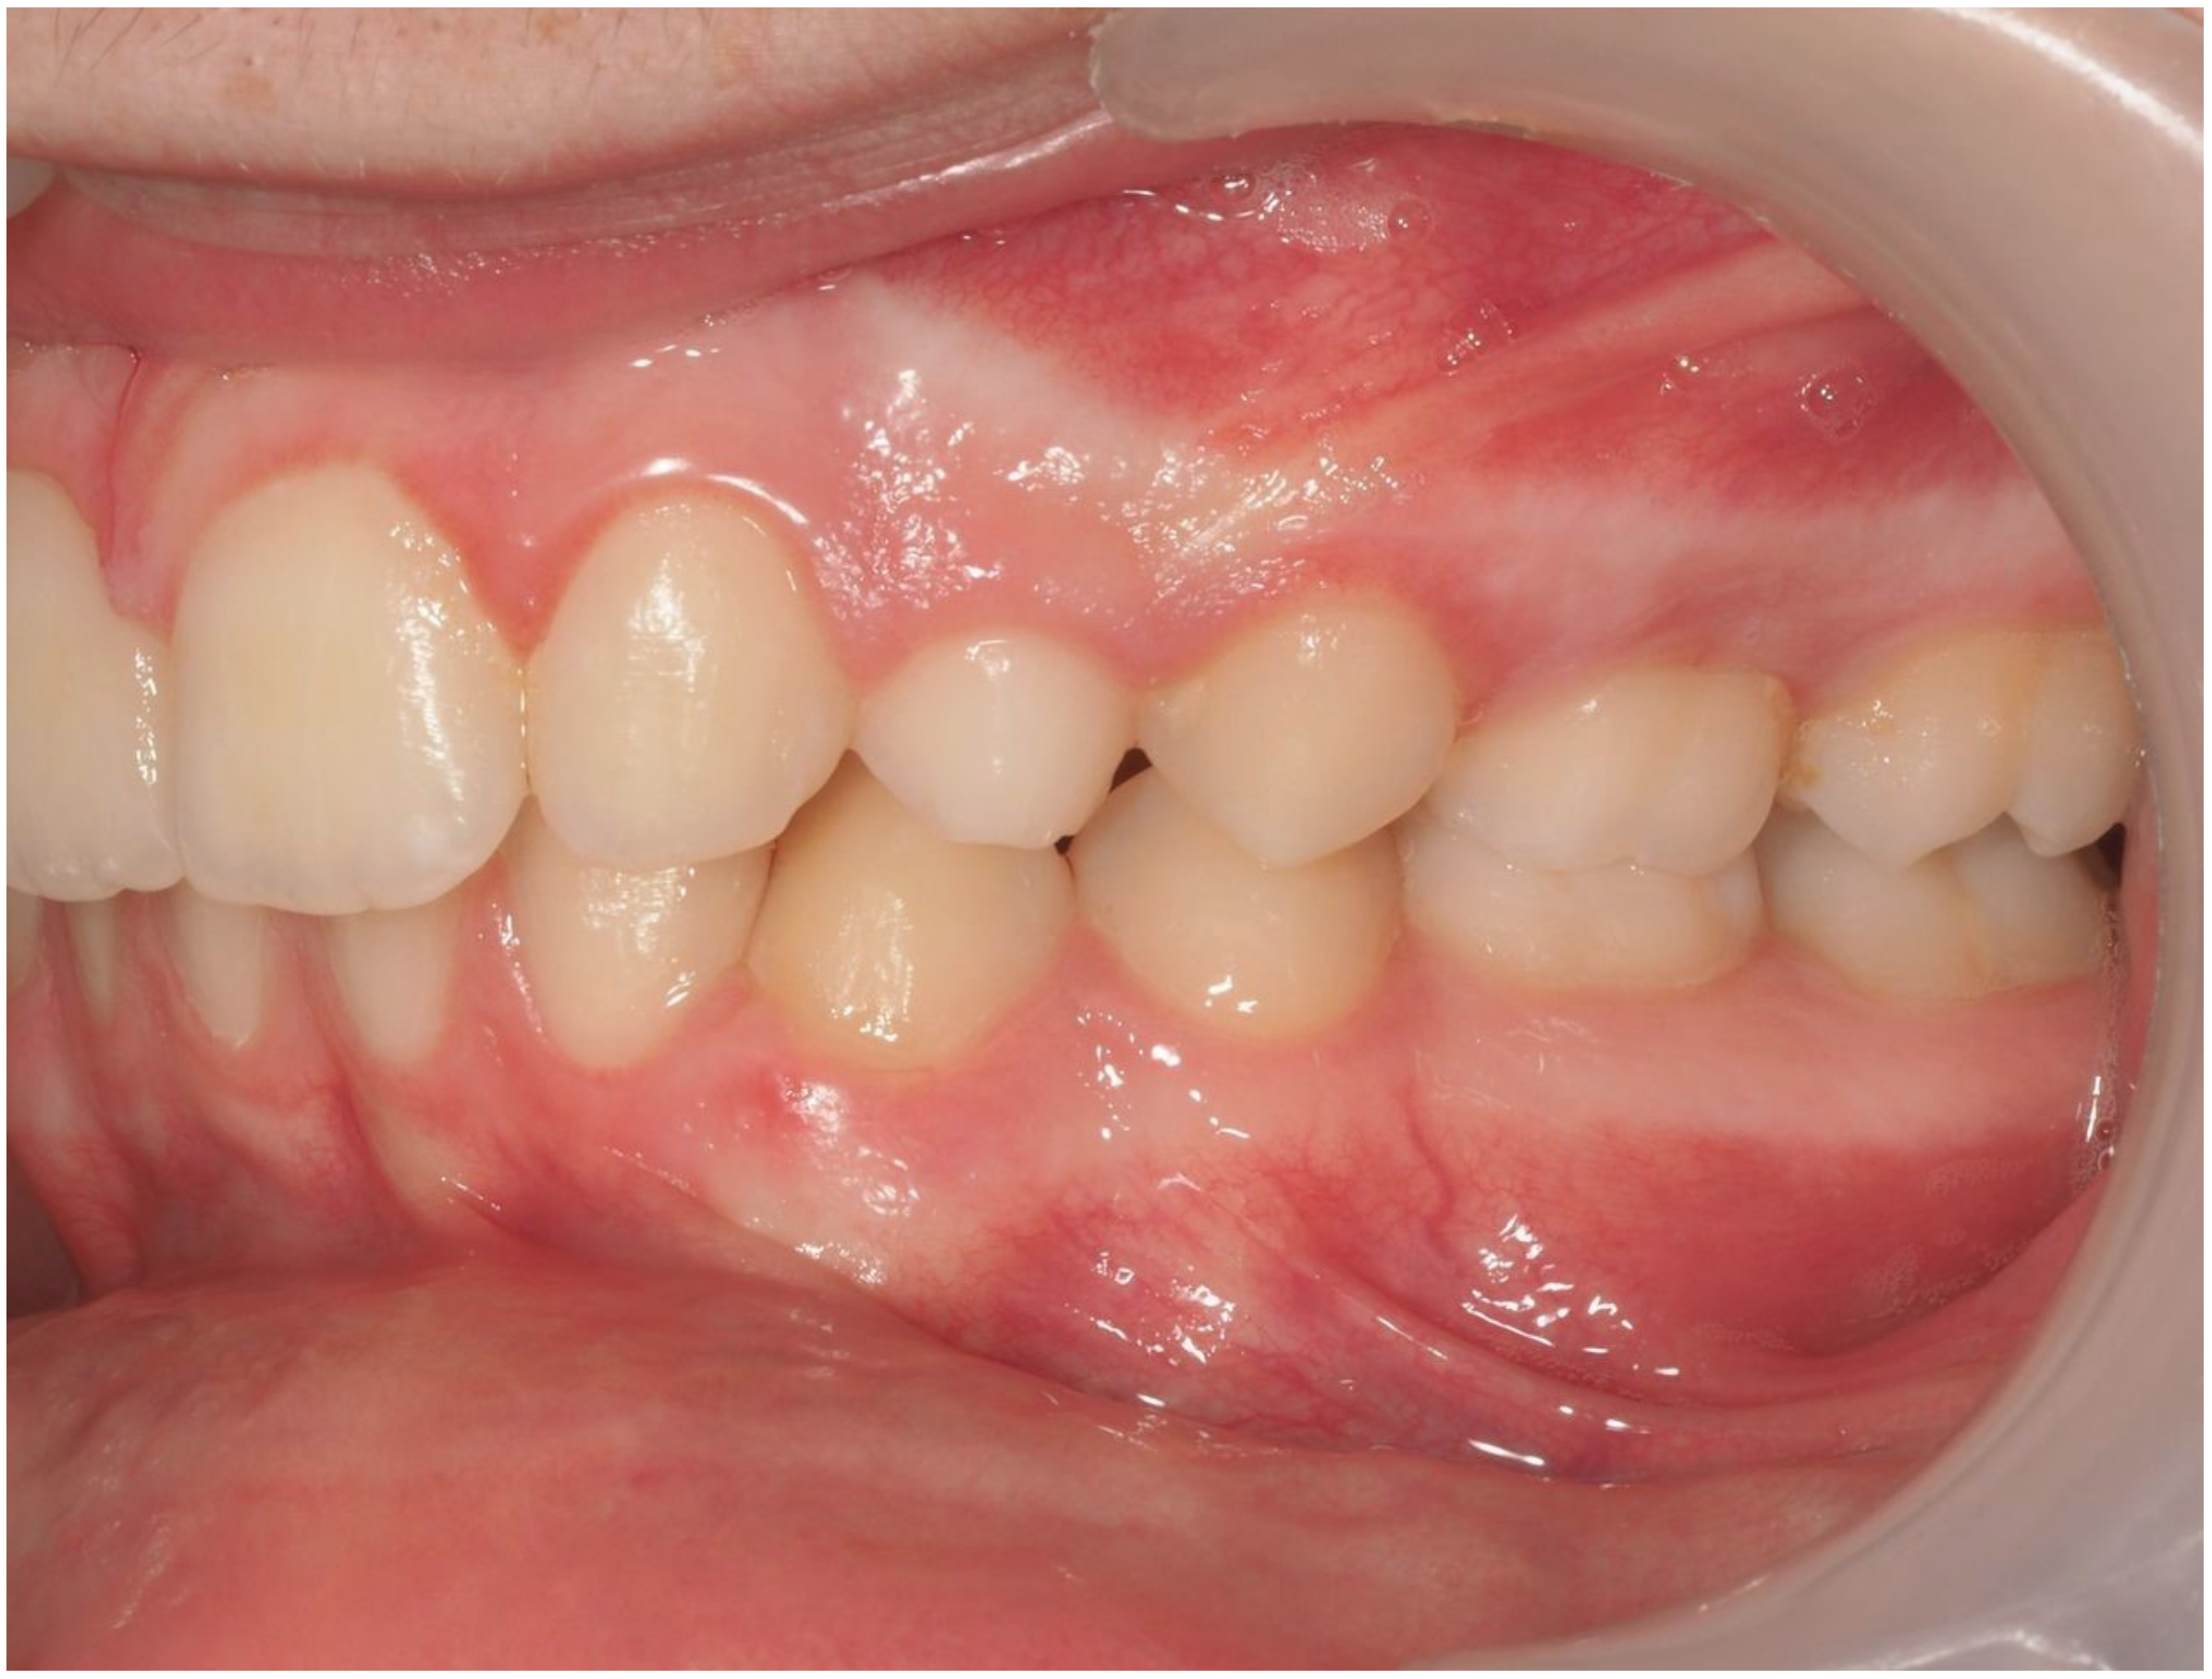

3.2. Representative Clinical Case

A 13-year-old male patient presented with Class II Division 2 malocclusion, a bilateral Class II sagittal relationship, and retroclined incisors. Cone-beam computed tomography revealed a palatally impacted maxillary left canine (tooth 23), with its cusp located palatally to the apical half of the left lateral incisor. The root exhibited significant apical curvature, extending toward the floor of the maxillary sinus (Figure 12 and Figure 13), making spontaneous eruption unlikely.

Figure 12.

Initial intraoral lateral photo.